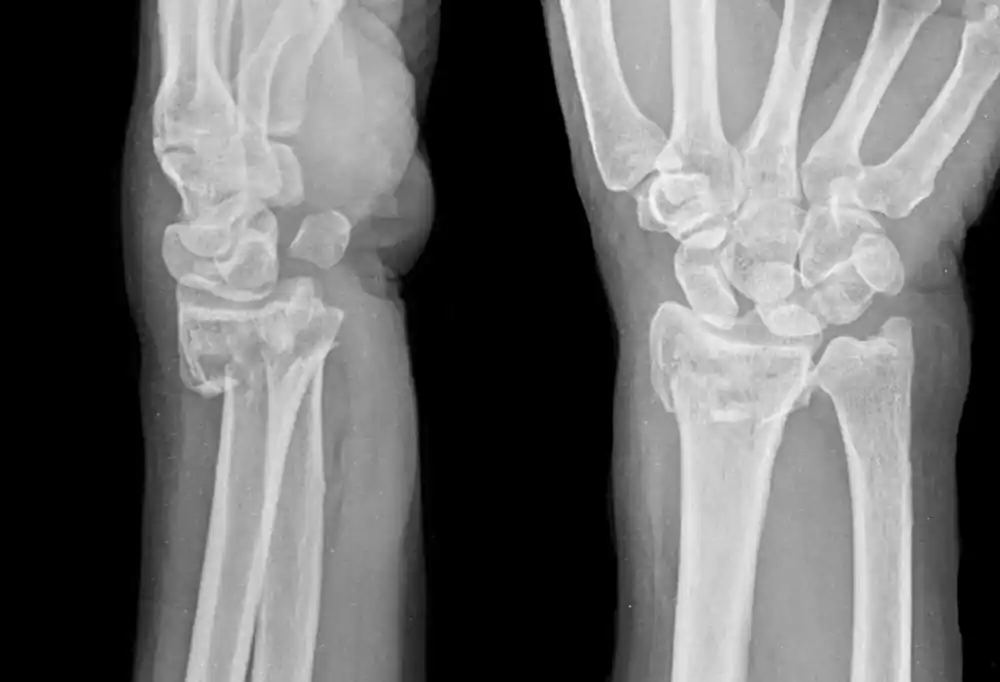

Distal radius kırığı, ön kolun başparmak tarafındaki kemiği olan radiusun, bileğe yakın kısmında meydana gelen kırıklardır. Genellikle elin üzerine düşme sonucu oluşur ve oldukça yaygındır.

Doktor, fizik muayene yaparak ve şu tetkikleri kullanarak kırığı tespit edebilir:

Distal radius kırığının tedavi edilmesi, kırığın türüne ve şiddetine göre değişir. Hafif kırıklarda basit tedavi yöntemleri uygulanabilirken, daha ciddi kırıklarda cerrahi müdahale gerekebilir.